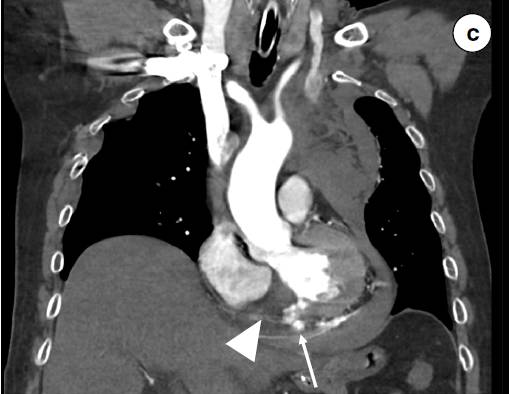

a 心电图显示Ⅱ、Ⅲ、aVF导联出现ST段抬高及Q波。 b 轴位CT扫描图像显示造影剂渗漏到心包、纵隔(三角形箭头)以及左侧胸腔的血性积液中(长箭头)。冠状位(c)和矢状位(d)CT重建显示造影剂从左心室向心包渗漏(长箭头)和右心室壁相对比的低密度影(三角形箭头)。